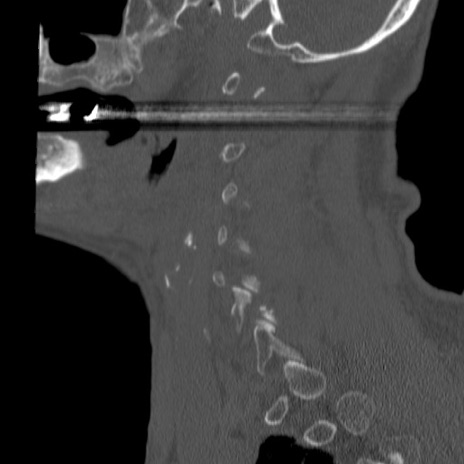

症例46 頚椎CT(矢状断像)

【症例】80歳代男性

【主訴】両側頚部〜上肢のしびれ

【現病歴】昨日、自宅内で転倒、その後より上記症状あり。意識障害なし。

【身体所見】両側上肢のallodynia(熱痛覚過敏)あり。MMTおよびDTRは正確な所見取れず。両上肢の挙上はなんとか可能。

異常所見と診断は?